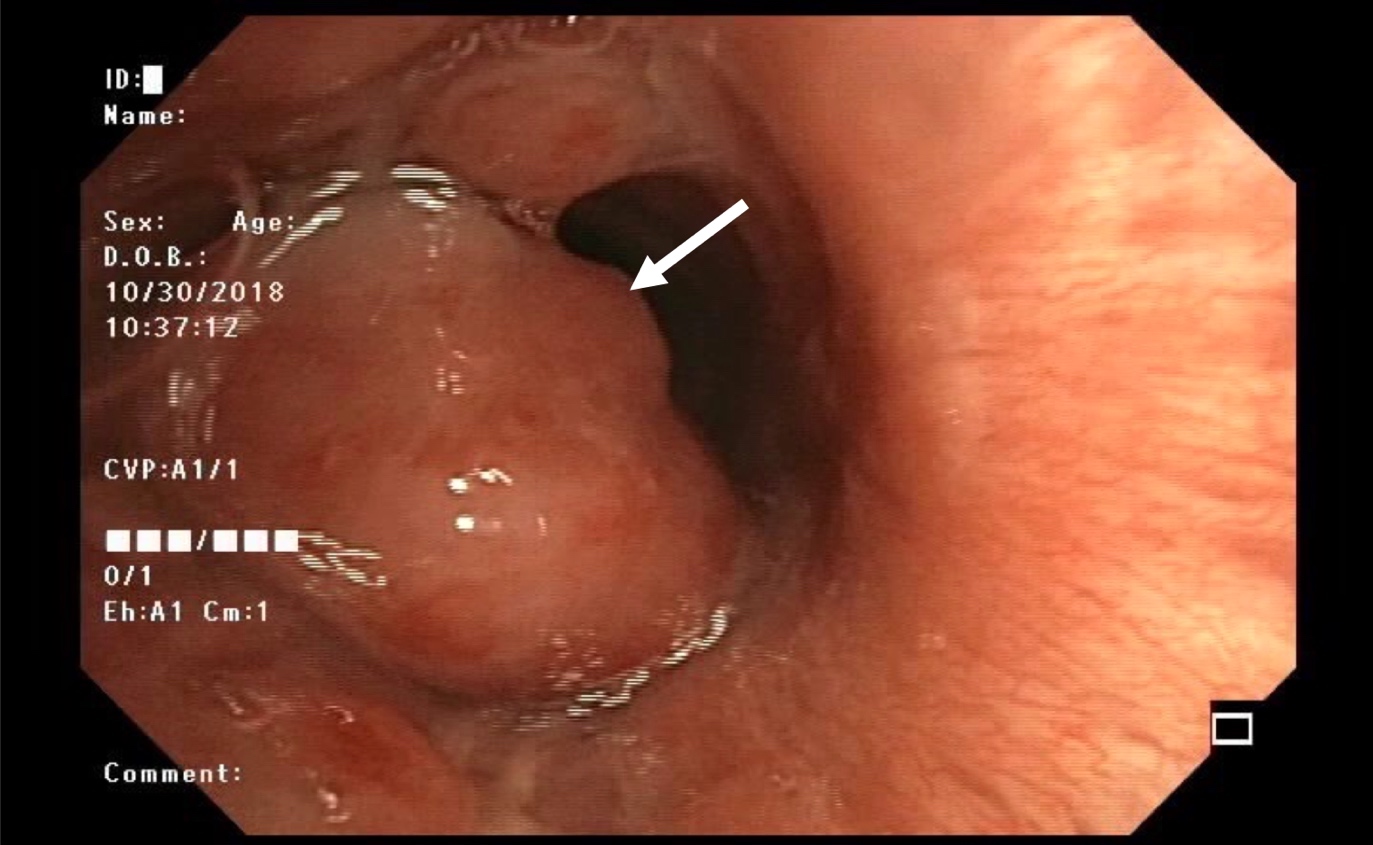

- Bronchoscopy shows polypoid endobronchial lesion in central airway

- Diagnosis of carcinoid can be made on biopsy or cytology specimen but the distinction between typical and atypical carcinoid usually requires a surgical specimen, unless necrosis or mitoses are seen (Ann Oncol 2015;26:1604)